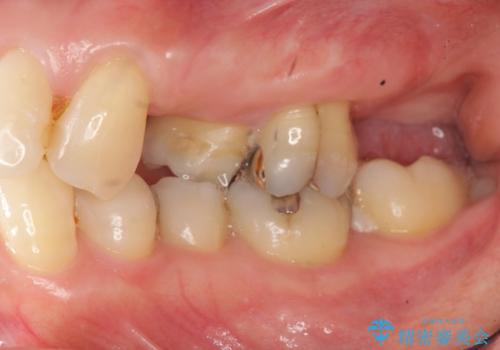

- 左上の歯の喪失し噛みにくいことの改善、歯を入れたいと希望され来院されました。

インプラント治療を行うには隙間が狭すぎるためブリッジか入れ歯をご提案したところ、取り外しの必要な入れ歯は希望されずブリッジを用いて機能・審美性の改善を行っていくこととなりました。